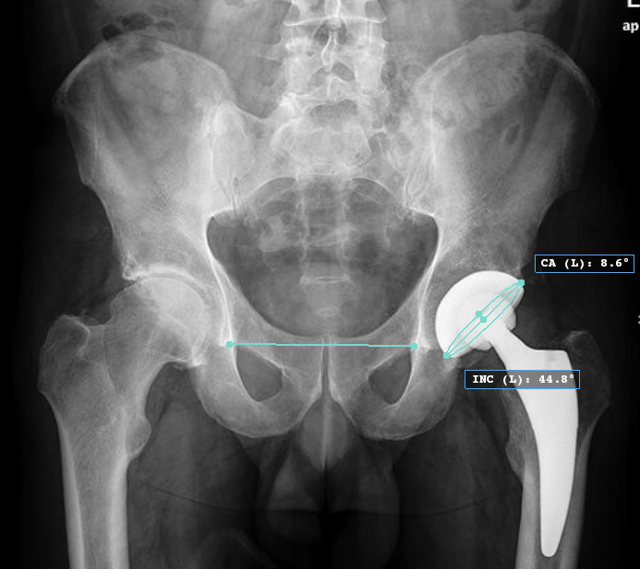

Acetabular Cup Position How to perform Types Of Acetabular Cups The common treatment options for acetabular cup revision are described below. Following preparation of the acetabulum, the trial cup is attached to the universal handle and is inserted into the acetabulum. They usually have a polyethylene liner. A metal shell for bony ingrowth + a liner to articulate with femoral head. Acetabular cup revision can be performed using uncemented. A. Types Of Acetabular Cups.